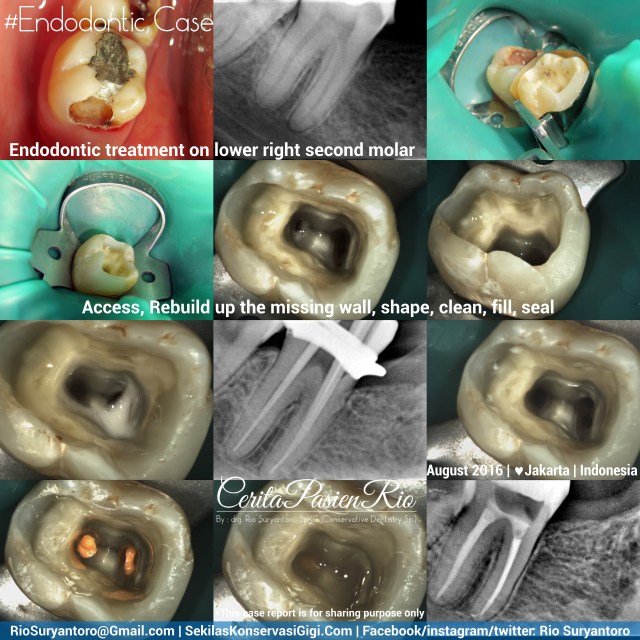

Endodontic treatment on lower right second molar

I got referral case from Dr. Vivi (dentist in Jakarta) to treat an endodontic treatment on lower right second molar with apical lesion from endodontic origin.

This case will give the way of creating 4 walled cavity access before endodontic treatment

After taking proper informed consent, i started my dental treatment. I did cavity access before placing rubber dam (hu friedy rubber dam clamp and blossom rubberdam sheet) and greatercurve matrix. As first molar is missing, i used the matrix also as a clamp. Then i put composite resin (filtek Z350XT) to build the mesial wall.

Shaping was done with Mtwo files (VDW) with clockwise reciprocal motion and rotary motion with I-mate2C endomotor (Denjoy). Cleaning with Natrium Hypochlorite 5,24% (generic) and EDTA 18% sol (ultradent). Obturation with gutta percha and EndoRez sealer (ultradent) and coronally sealed with low shrinkage stress flowable composite resin (filtek bulkfill flowable – 3m).